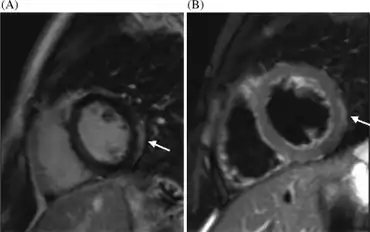

Cardiac magnetic resonance imaging (cMRI or CMR) has been shown to be very useful in diagnosing myocarditis by visualizing markers for inflammation of the myocardium.[28] Recently, consensus criteria for the diagnosis of myocarditis by CMR have been published.[29]